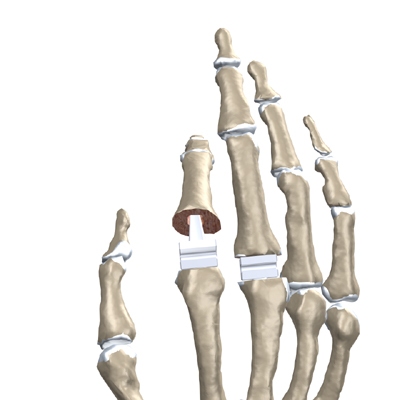

The surgeon then sizes the stem of the prosthesis to ensure a snug fit into the hollow bone marrow space of the bone. The prosthesis is inserted into the ends of both finger bones.

When the new joint is in place, the surgeon wraps the joint with a strip of nearby ligament to form a tight sac. This gives the new implant some added protection and stability.